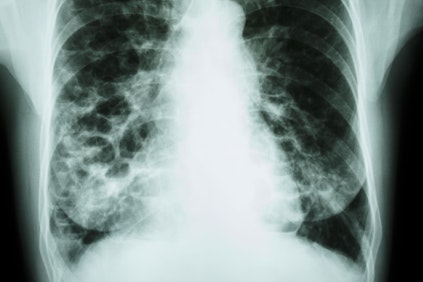

Pneumonia is a bacterial or viral infection that causes the air sacs within the lungs to become inflamed. It can result in moderate to severe symptoms that may include coughing, excess mucus production, fever, and difficulty breathing. The disease can be life-threatening for babies, seniors, and patients with other health conditions. Antibiotics are the most common treatment for bacterial pneumonia.